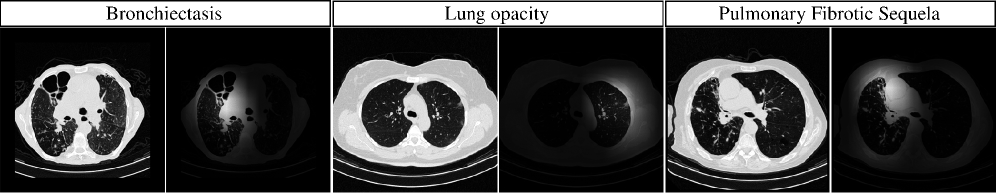

For each method and each label, we select the threshold that maximizes F1-Score on the validation set and report all metrics on the test set. We compare our method against ViViT [2], a video-adapted Vision Transformer which also forms the architectural basis for CT-ViT, and Swin3D [34], an extension of Swin Transformer for volumetric data. We also include CT-Net [13] and CT-Scroll [11], two 2.5D approaches that employ CNN-based feature extractors. CT-Net relies on convolutional layers for feature aggregation and dimensionality reduction, whereas CT-Scroll leverages an alternating attention mechanism to capture cross-slice dependencies. ResNet-based models used ImageNet pre-trained weights; others were initialized via weight inflation [36] for comparability. Table 1 shows that CT-Graph consistently outperforms all baselines across AUROC, F1-Score and Recall. On the CT-RATE test set, our method achieves an F1-Score of 54.5954.5954.59, representing a +Δ\Deltaroman_Δ1.15% improvement over CT-Scroll [11] and +Δ\Deltaroman_Δ5.93% over CT-Net [13]. For the F1-Score, a paired t-test comparing the performance of CT-Graph against each baseline consistently yields a p-value <0.01<0.01< 0.01, demonstrating statistical significance. As shown in Fig. 3.a, CT-Graph yields the largest improvements on diffuse anomalies such as bronchiectasis, mosaic attenuation, and lung opacity. Reffering to Fig. 3.b, both attention and spectral convolution demonstrate robustness to z-axis translations, whereas standard convolution is sensitive to such shifts. To evaluate this property, we simulate patient body shifts by applying controlled translations along the z-axis with appropriate padding.